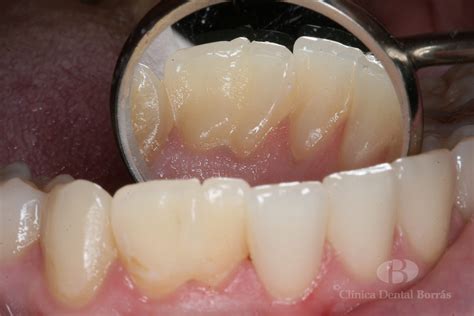

Diagnóstico

El diagnóstico de los dientes en tecla de piano habitualmente es casual, ya que suele ser asintomático. Algunas de estas anomalías son más que evidentes clínicamente, y otras pueden pasar desapercibidas para el profesional. Se realiza mediante una exploración intraoral exhaustiva, donde se observa la morfología atípica de la corona dental.

- Susceptibilidad a caries: Los surcos y crestas pueden dificultar la higiene dental, aumentando el riesgo de acumulación de placa y caries.

- Riesgo de lesión pulpar: La alteración en la forma del diente puede comprometer la estructura del esmalte y la dentina, aumentando el riesgo de exposición y daño a la pulpa dental.